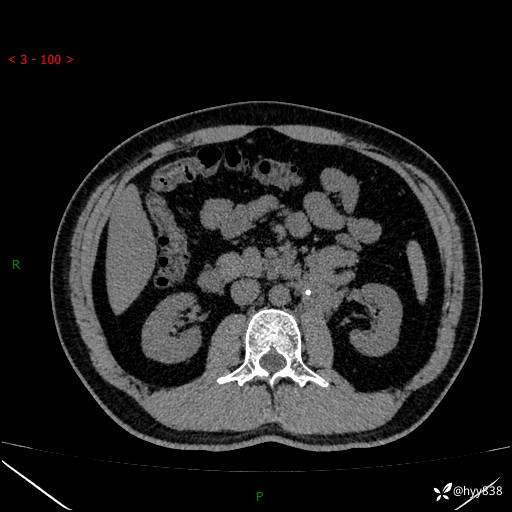

现病史:患者3月余前检查发现左侧腹膜后占位,大小约3.7*4.9cm,平素无腰疼,无肉眼血尿,无尿频尿急等不适,当时未特殊处理,在门诊复查CT提示左侧腹膜后占位,门诊拟“左侧腹膜后占位”收入院。 起病以来,患者精神佳,饮食、睡眠良好,大小便正常,体力体重无明显变化。

腹膜后CT平扫+增强